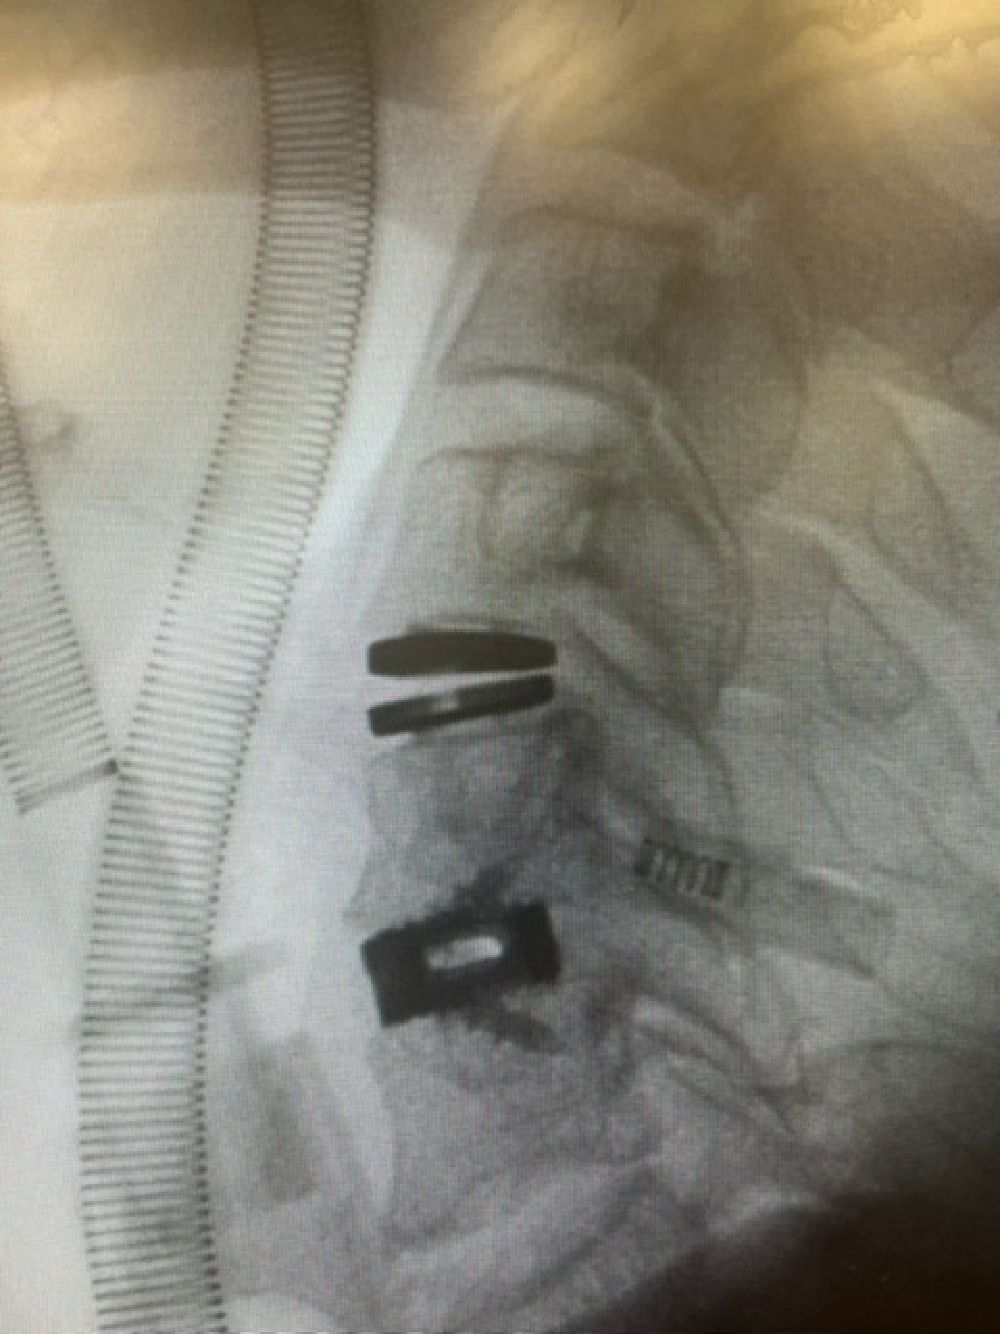

Patologia Degenerativa da Coluna Vertebral

- Tratamento de doenças que afetam a estrutura e função da coluna, com potencial impacto na qualidade de vida.

- Hérnia discal